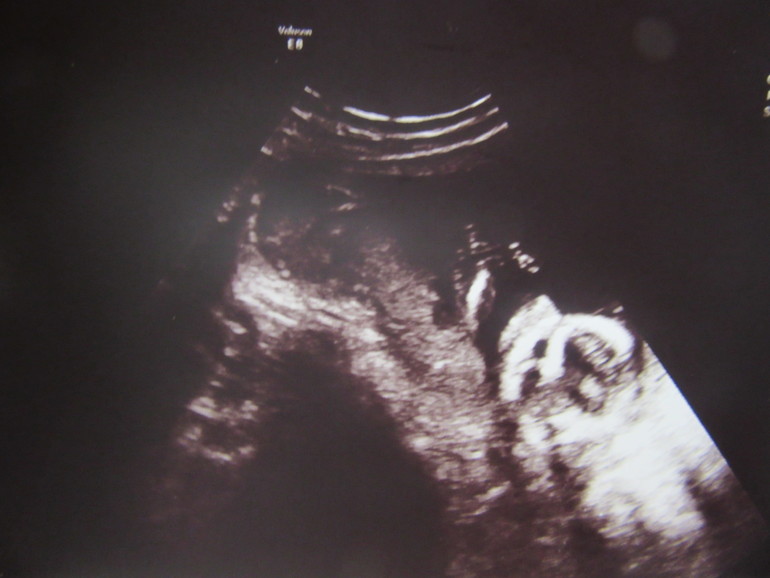

Вчера мы ходили на узи,нам сказали девочка,поэтому пузожитель теперь переходит в статус МАЛЫШКА))))А еще меняю цвет кружочка!!!Мужу ничего не сказала,сказала просто в поликлинику,пошла в Ультрамед на 3д к Цецулиной. Ходила с сестрой,она еще не нагуляла интерес к детям,хотя мы погодки,так что я делаю это своей целью теперь)))Я очень трусила,боялась заходить,готовилась еще давно морально к Ванюше,ведь в 12 нед на скрининге горежкврач сказала мальчик,но надежда на девочку теплилась,сестра обнимала говорила не ссы, и Боженька ведь все сам рапределяет)))Врач очень доброжелательная,как и говорила моя сноха, я с ходу ,пока ложилась сказала нам нужно пирожочек найти,т.к. 2 стручка дома уже сидят)Она с первых же секунд нашла лягушачьи лапки и показала пирожок)Сказала 80% девочка из-за срока,маловат,но сказала что уверена что вряд ли что-то отрастет)))Вообщем поумилялись мы на жемчужную цепочку позвоночника, ножки ручки,малышка лежит ноги и руки к лицу,скрючилась ужас)Показали нам и 3д,я сразу уже все разбираюсь где да что)сестре тяжелее было сорентироваться. Личико увидела.Мне кажется малышка будет похожа на Матюшу,т.е на папу.Вес крошки 163 гр)СБ 148 уд/мин. После пошли в пиццерию,порадоваться немного сестрой,она будет крестной))))))Кому интересно фото и видео ниже.

Грушу я в Ашане как дурак выбирала,конечно,бугагга)))каждую взвешивала,суббота,толпа,а я взвешиваю,выбрала 140 граммовую,а малышка уже 163 гр!!!!